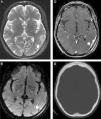

Magnetic resonance spectroscopyProton magnetic resonance spectroscopy (MRS) allows for the semiquantitative evaluation of in vivo tissue to measure metabolites, such as N-acetylaspartate (NAA), choline (Cho), creatinine (Cr), lactate (Lac), and lipids (Lip). In PCNSL, MRS has demonstrated elevated Lip and Lac peaks, high Cho/Cr ratios, decreased NAA levels and high Cho/NAA ratios (Figure 1).4,11,16,17 The presence of Lac or Lip at baseline has been associated with poor progression-free and overall survival.11

Diffuse large B-cell lymphoma in the corpus callosum. An axial T1 image after intravenous gadolinium administration (A) shows a homogeneous enhanced mass in the splenium of the corpus callosum, which is predominantly in the right hemisphere (arrow). An axial apparent diffusion coefficient map (B) confirmed a very low signal intensity in the solid lesion. Note the hyperintensity of the perilesional vasogenic edema. Proton magnetic resonance spectroscopy (C) shows decreased N-acetylaspartate levels and high choline/N-acetylaspartate and choline/creatinine ratios. Note the increased lipid and lactate peaks (0.9–1.3ppm). A magnetic resonance perfusion sequence (dynamic susceptibility contrast magnetic resonance image T2*) (D) confirmed the absence of neoangiogenesis (low relative cerebral blood volume). Note the high percentage of signal intensity recovery (the ascending part of the curve above the baseline as indicated by the vertical arrowheads).

PCNSL grow rapidly and behave similar to high-grade brain tumors with evidence of high cell membrane turnover on MRS (a high Cho peak), neuronal damage (decreased NAA levels), and anaerobiosis (high lactate levels).4,11,16,17 These findings are similar to those for high-grade gliomas and metastases; however, the presence of this MRS pattern may help in the differential diagnosis of brain toxoplasmosis in immunocompromised patients, which typically exhibits elevated Lip peaks and no significant increases in Cho or its ratios.1,4,11